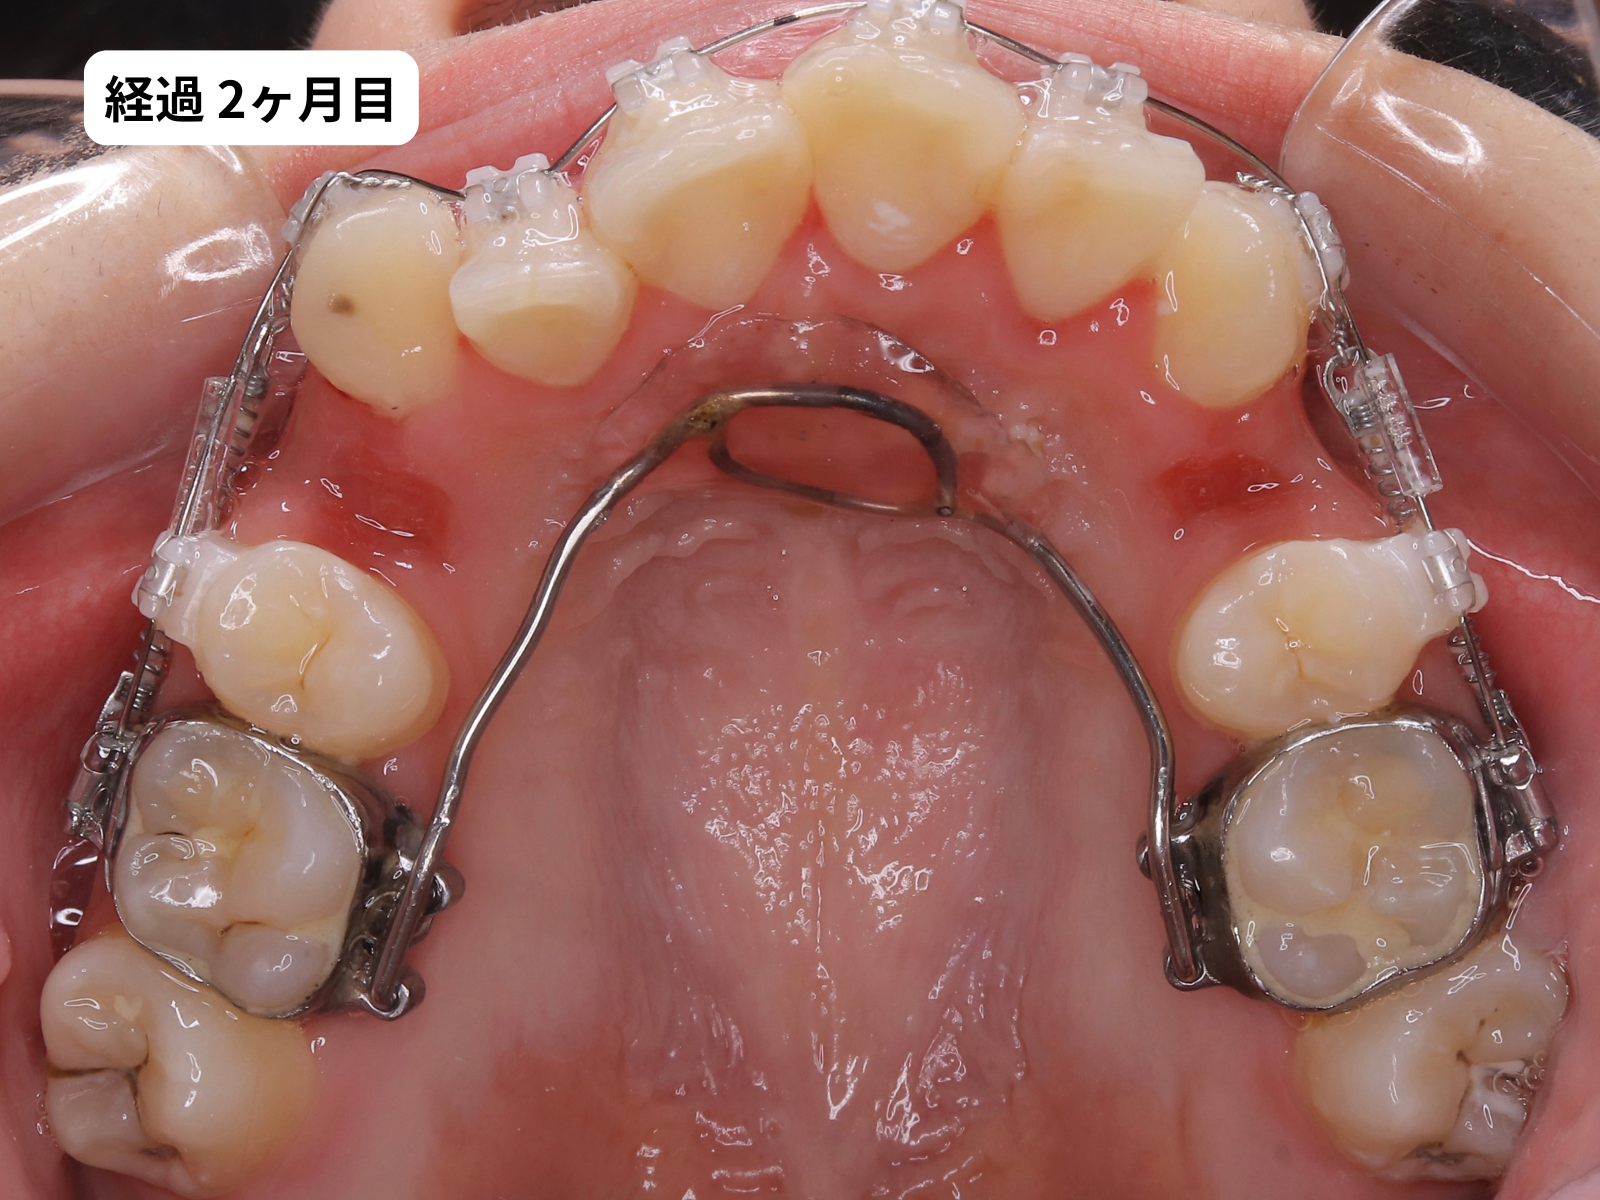

装置装着から1年2ヶ月、毎月の経過

装置をつけた後、上の歯の噛み合わせ面の写真を毎月記録しました。下のスライダーで、月ごとに歯がどう動いていったかをご覧いただけます。

毎月の写真で歯がスムーズに動いているのがわかります。これは 軽い力(約50g)でゆっくり動かす、毎回の来院で移動距離を確認する、この2つを積み重ねた結果です。